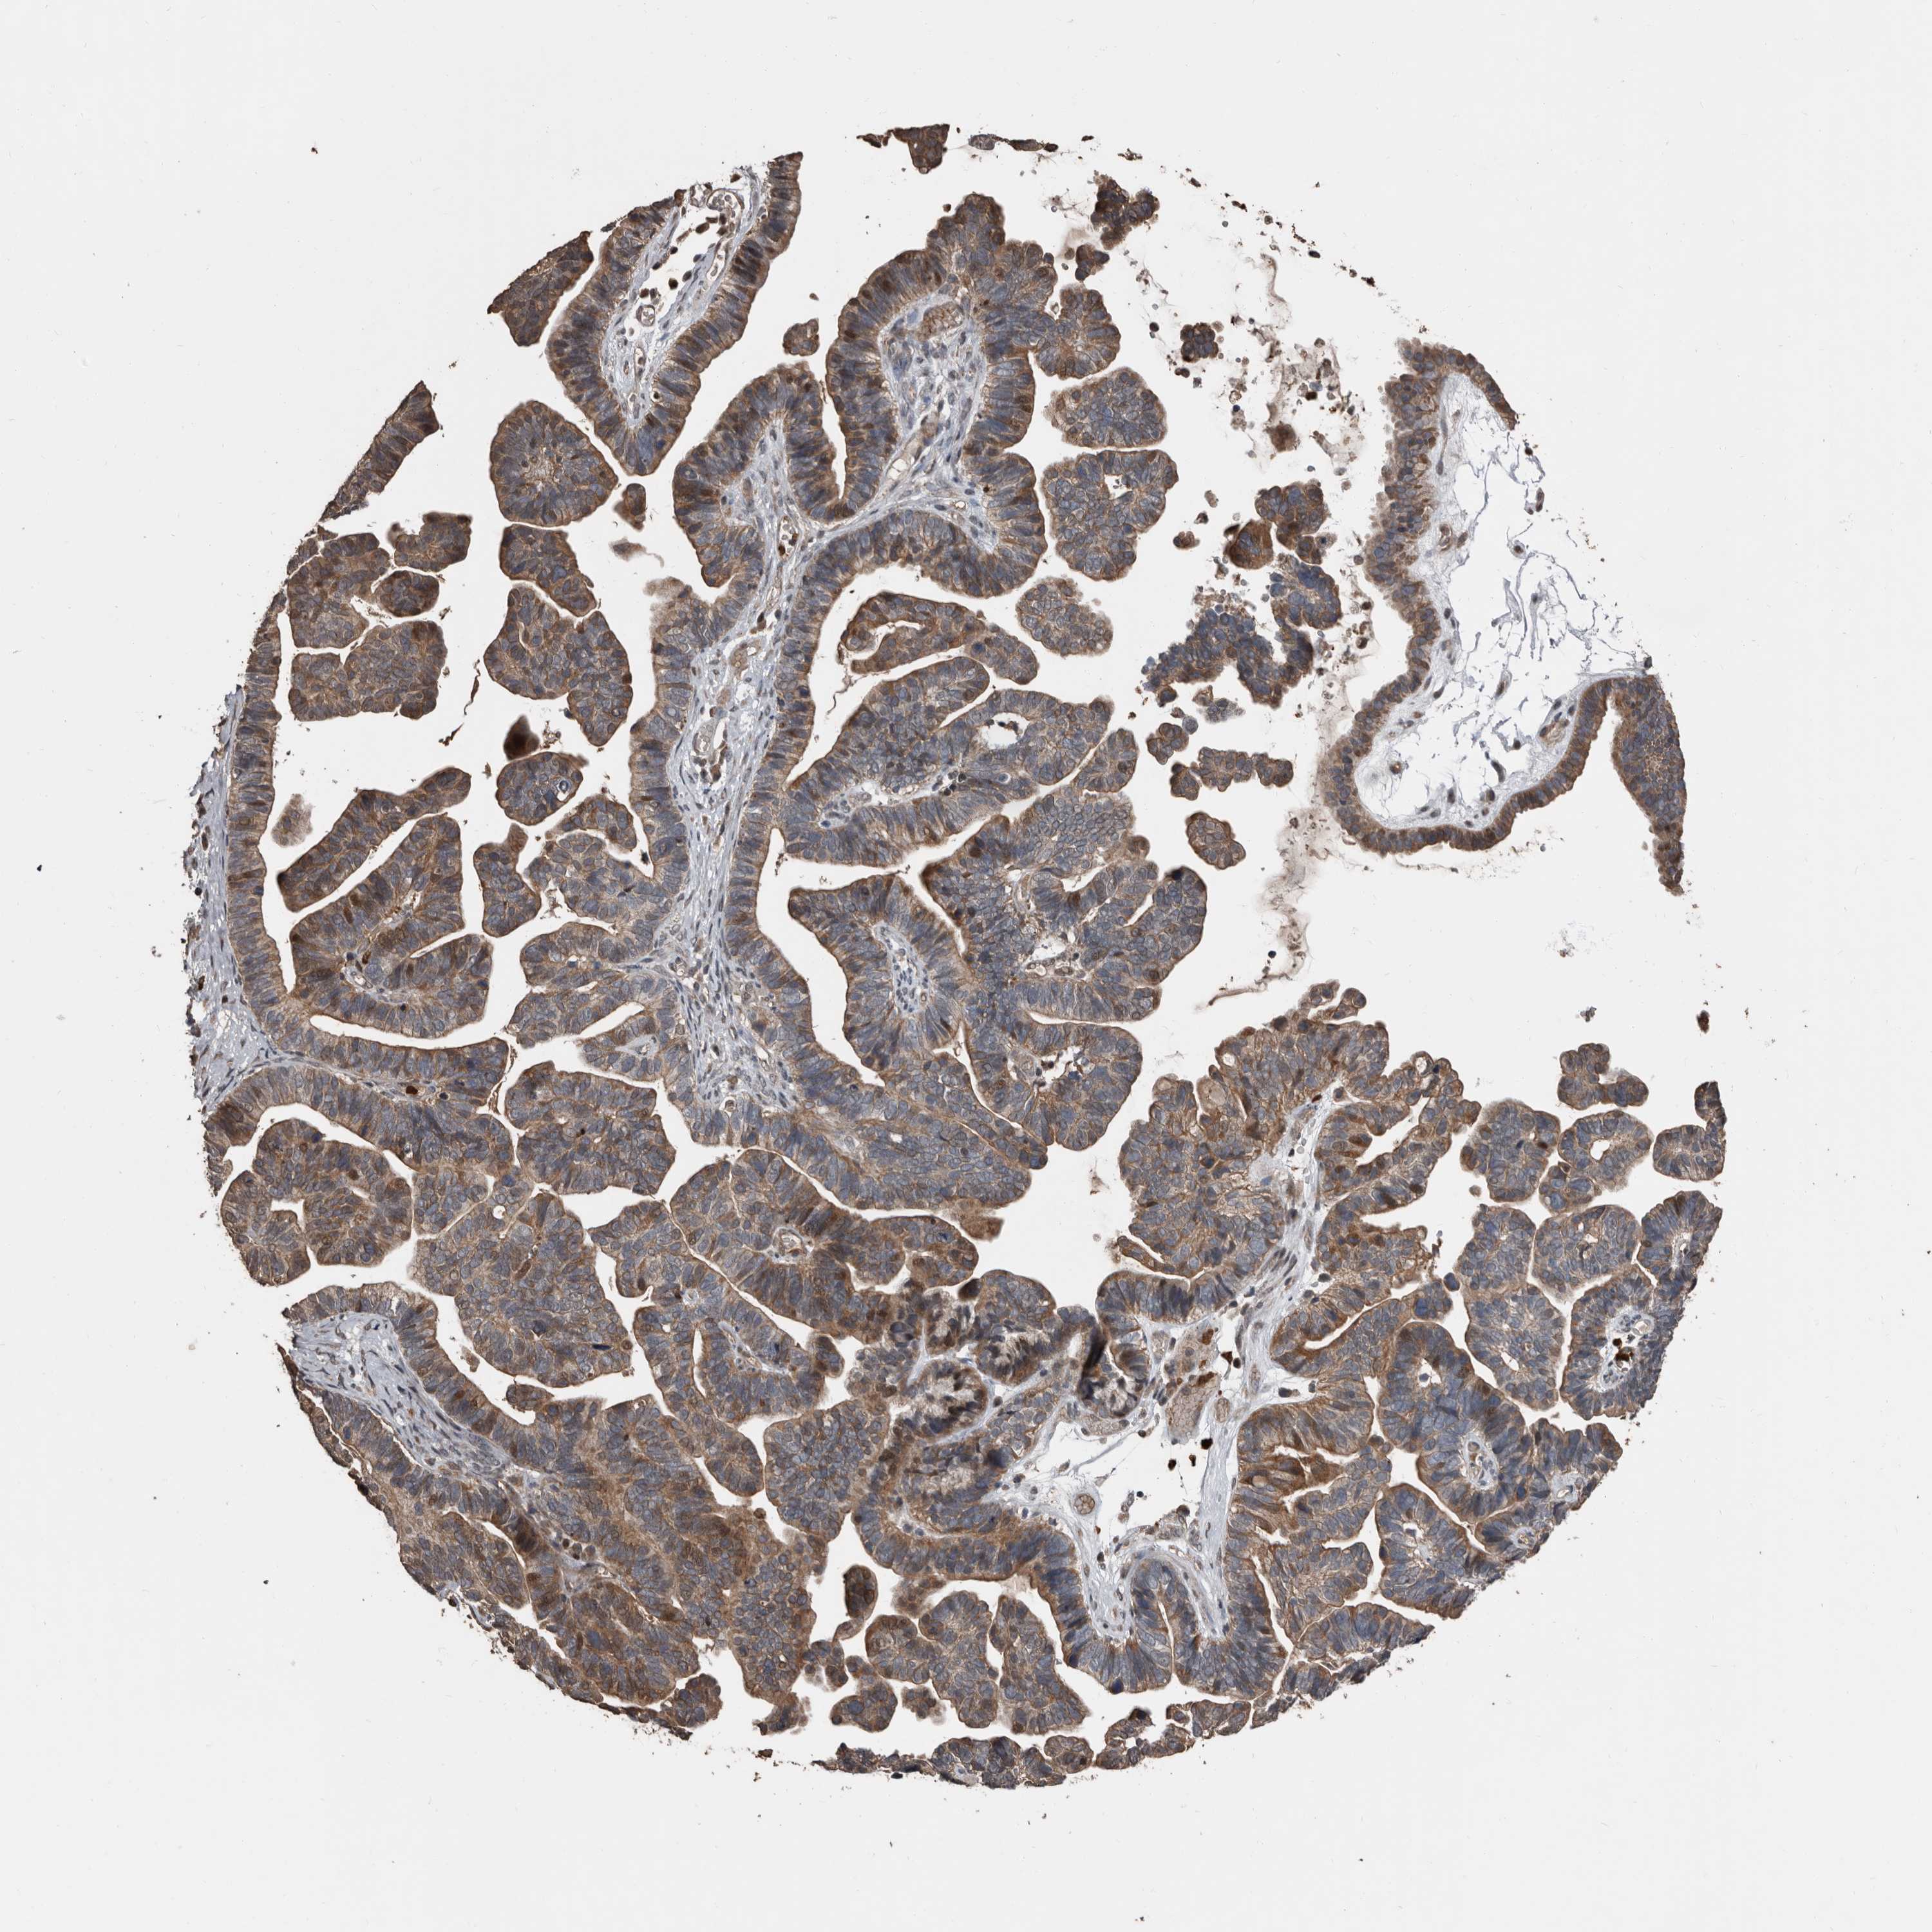

OVARIAN CANCER - Protein expressioni

A mouse-over function shows sample information and annotation data. Click on an image to view it in a full screen mode. Samples can be filtered based on level of antibody staining by selecting one or several of the following categories: high, medium, low and not detected. The assay and annotation is described here.

Note that samples used for immunohistochemistry by the Human Protein Atlas do not correspond to samples in the TCGA dataset.

Antibody stainingi

Antibody staining in the annotated cell types in the current human tissue is reported as not detected, low, medium, or high, based on conventional immunohistochemistry profiling in selected tissues. This score is based on the combination of the staining intensity and fraction of stained cells.

Each image is clickable and will lead to virtual microscopy that enables deeper exploration of all samples and also displays staining intensity scores, fraction scores and subcellular localization as well as patient and tissue information for each sample.

Antibody HPA026509

Staining

High

Medium

Low

Not detected

Intensity

Strong

Moderate

Weak

Negative

Quantity

>75%

75%-25%

<25%

None

Location

Nuclear

Cytoplasmic/membranous

Cytoplasmic/membranous,nuclear

Cystadenocarcinoma, serous, NOS

Carcinoma, endometroid

Cystadenocarcinoma, mucinous, NOS

Carcinoma, NOS